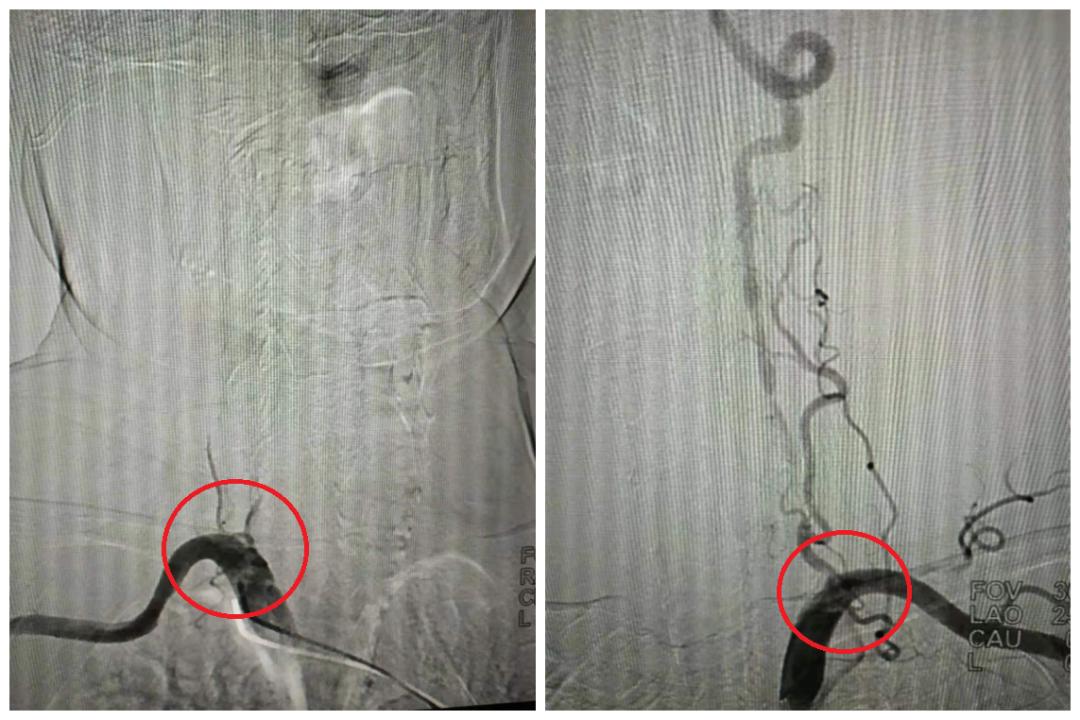

双侧椎动脉起始段闭塞(局部),右图含侧支代偿

双侧颈动脉C1段狭窄(局部)